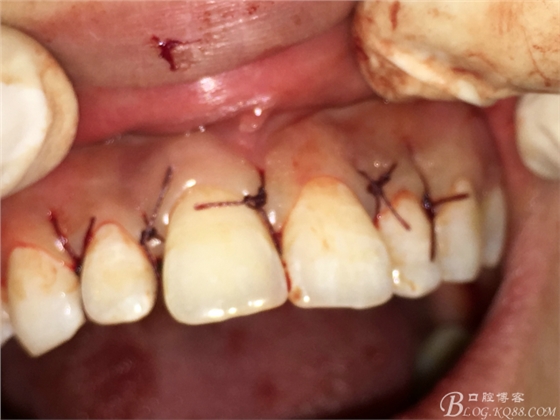

圖18.縫合